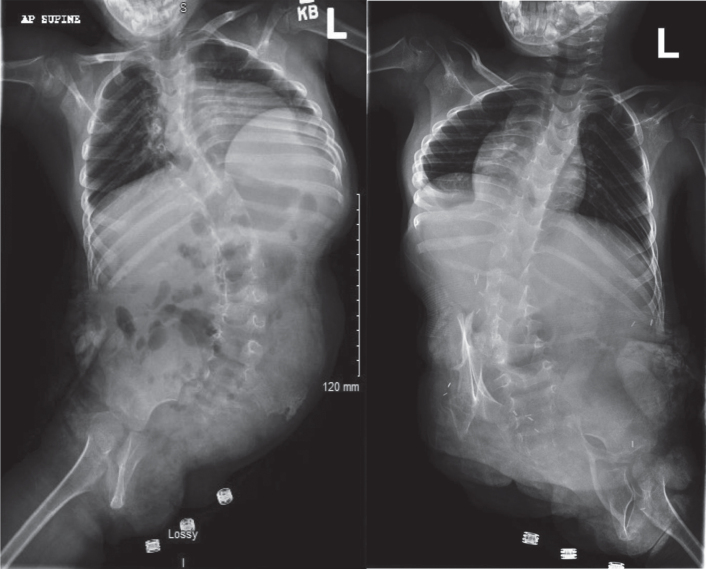

Conjoined twins are identical twins joined in utero and are a rare phenomenon. This report discusses a case of female thoraco-omphalo-ischiopagus tripus conjoined twins. The twins were separated at age two, and once medically stable, spent one month in inpatient rehabilitation to improve their sitting balance and gross motor skills. This was followed by outpatient physical therapy. The twins initially had customized ZipZac seats, which they were able to wheel independently. After six months of therapy, the girls began walking with posterior walkers and prostheses. The hemipelvectomy prosthesis included a customized thoracolumbosacral orthosis component and was directly attached to a non-articulated pylon. A manual-locking hip joint was added to accommodate sitting. An articulated ankle-foot orthosis was used for the intact leg. Care of formerly conjoined twins requires comprehensive care from a multidisciplinary team involving, but not limited to, a physiatrist, orthopaedic surgeon, physical therapist, and orthotist/prosthetist. Complex congenital limb deficiencies are often a major undertaking for the rehabilitation team as continuous treatment and management are needed throughout the patient's lifetime due to growth, development, and evolving physical demands. Anatomic variations must be examined on a case-by-case basis but often include limb deficiencies, orthopedic abnormalities, and organ comorbidities.